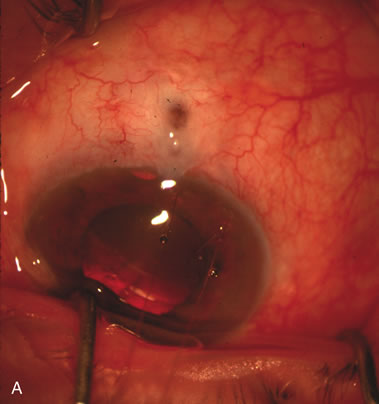

Fig. 3. Partial bleb failure following clear corneal phacoemulsification with foldable IOL. A. Preoperative bleb appearance prior to temporal lens extraction. Preoperative IOP was 12 mm Hg on no antiglaucoma medications. Time from 5-FU trabeculectomy surgery to lens extraction was one year. B. Bleb appearance 2 months after clear corneal cataract surgery with topical anesthesia. Following lens extraction, increased vascularity was noted along with decreased size of the filtering bleb. IOP increased to 20 mm Hg as early as 2 weeks after surgery, necessitating topical antiglaucoma therapy. C. High magnification view of bleb before lens extraction demonstrates diffuse pale bleb. D. High magnification view of bleb 2 months after surgery. There are vessels surrounding the nasal side of the bleb and the overall bleb size is smaller.